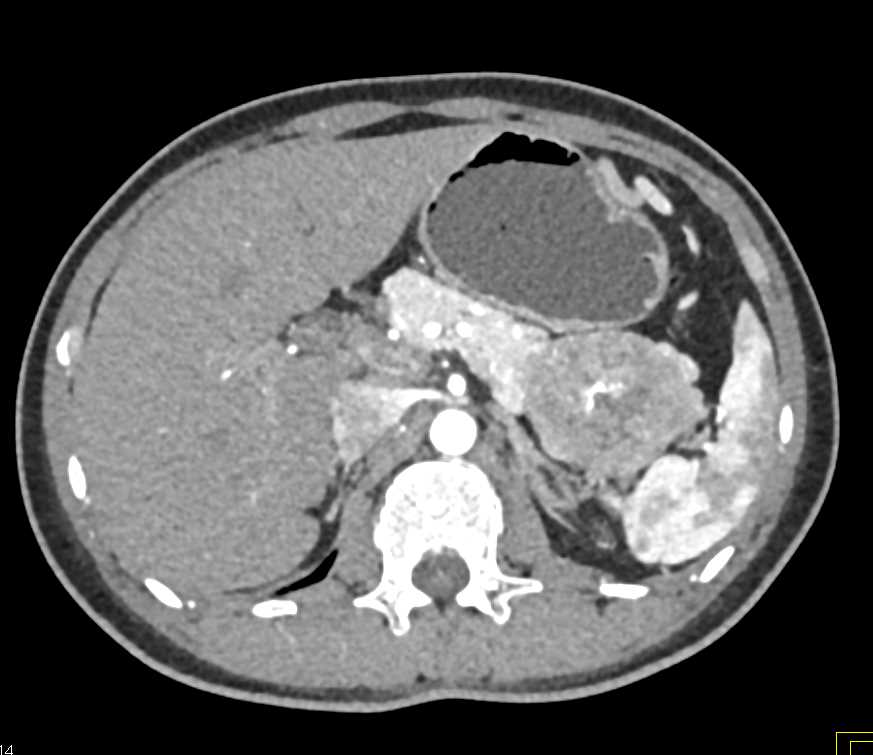

PNET Tail of the Pancreas